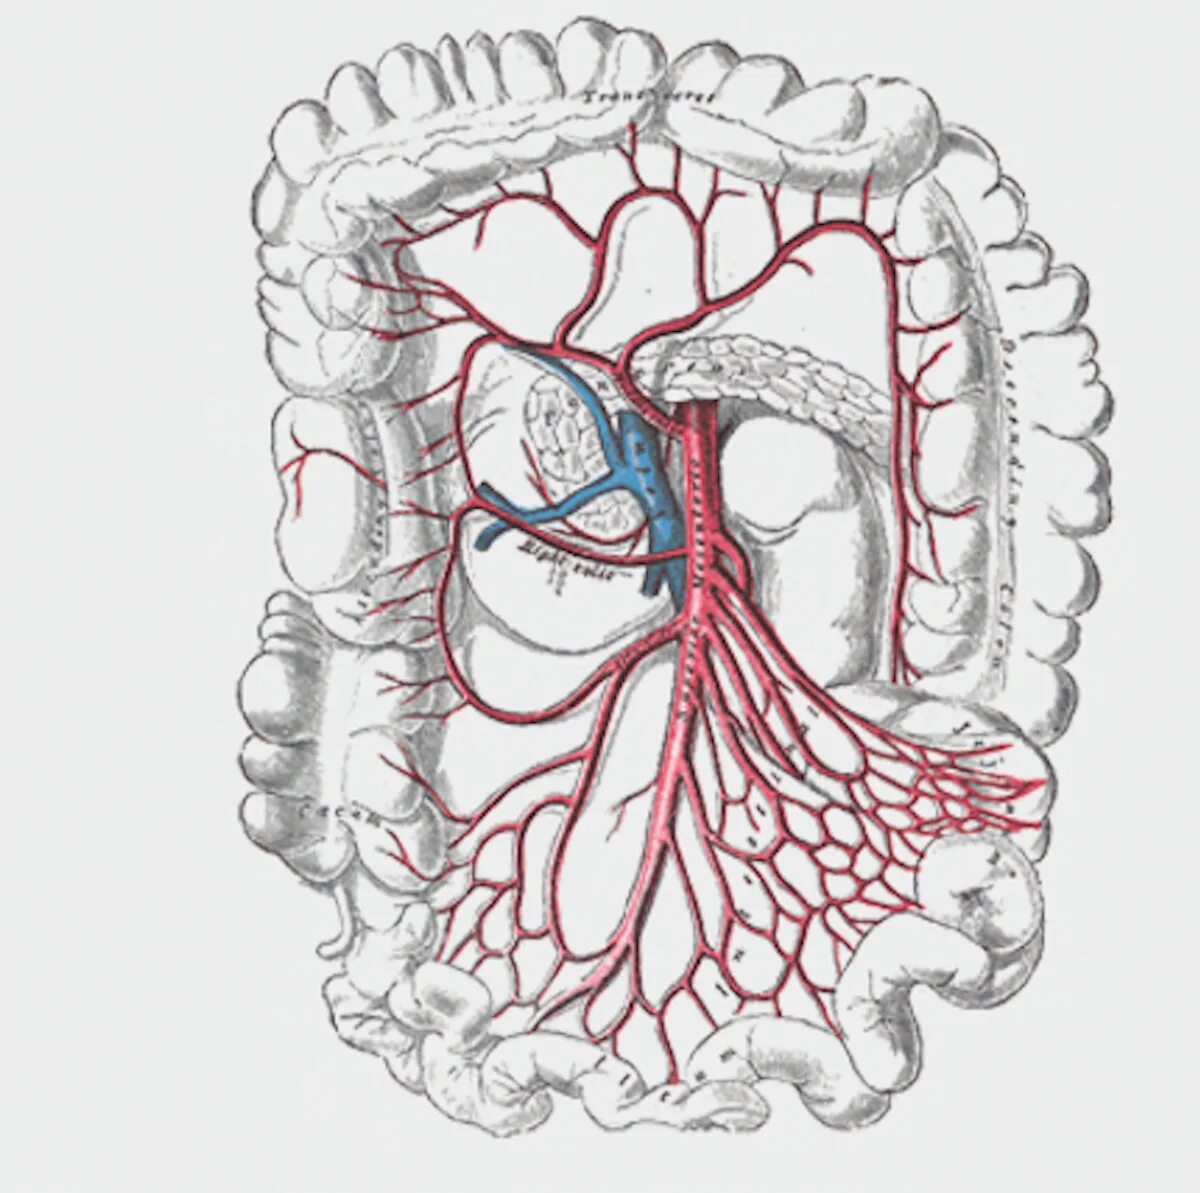

Тромбоз брыжеечной артерии